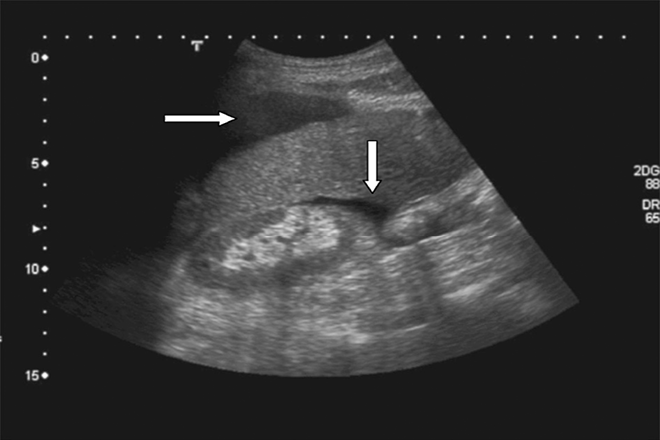

Ultrasonido con contraste de masas Hepáticas

El ultrasonido con contraste (en inglés, Contrast-enhaced Ultrasonography, CEUS) de hígado es un método usado para evaluar masas hepáticas. Ofrece una excelente resolución espacial y de contraste y puede mostrar cierta vascularidad con la técnica doppler, tiene limitaciones para caracterizar la vascularidad de las lesiones